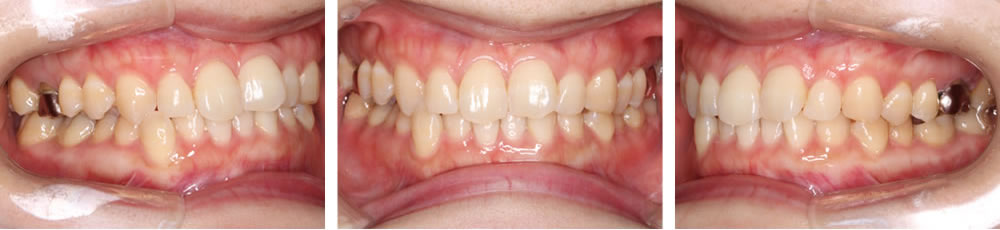

こちらの患者さまは、歯並びと咬み合わせが気になるとのことで来院されました。

術前は上下顎の正中がずれており、右下の犬歯が飛び出している歯並びでした。術後は上下の正中が揃い、理想的な被蓋関係で咬み合う、きれいな歯並びになりました。